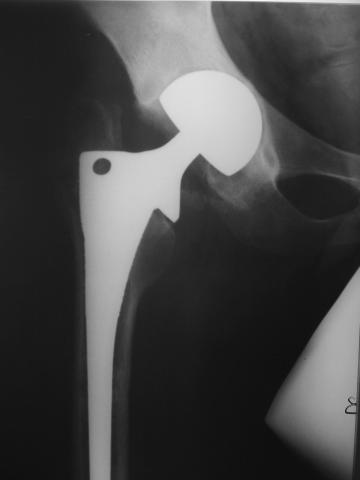

Уважаемые коллеги! молодой человек 22 лет обратился к нам с жалобами на умеренную боль в в/3 левого бедра и паху при ходьбе, укорочение левой ноги. 3 года назад получил закрытый перелом шейки левого бедра (рис 1).

Лечился в стержневом аппарате по месту жительства. АВФ демонтировали через полгода из-за воспаления в области стержней (рис 2). После демонтажа в течение месяца больной лихорадил до 38*, были боли в бедре. Эти явления исчезли после курса антибиотиков. Через год после травмы в ЦРБ ему имплантировали биполярный протез (рис 3). Рана зажила первично. Ходил с костылями, слегка приступая на ногу. На контрольных осмотрах выявлена прогрессирующая протрузия (рис 4-6).